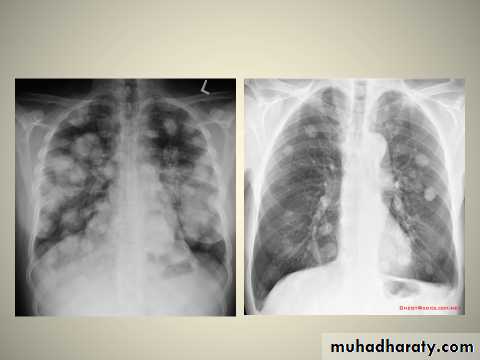

Multiple areas of opacity seen throughout the lung most often is due to bronchopneumonia, starting from bronchi and spreading outwards. Usually ill defined with peripheral distribution. Neoplasms such as a primary malignancy or metastasis can also cause this picture.

1.Cannonball metastases refer to large well circumscribed, round multiple opacities like cannonballs